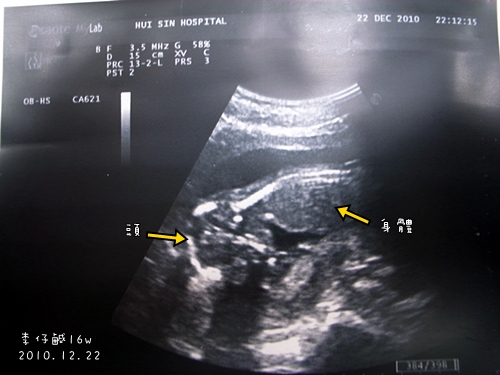

為何我的寶寶為何看不到性別..醫生還說他的腳像美人魚一樣彎曲重疊在一起..

醫生還說要等到4個月才看的到..

真的要等到這麼晚才知道性別..